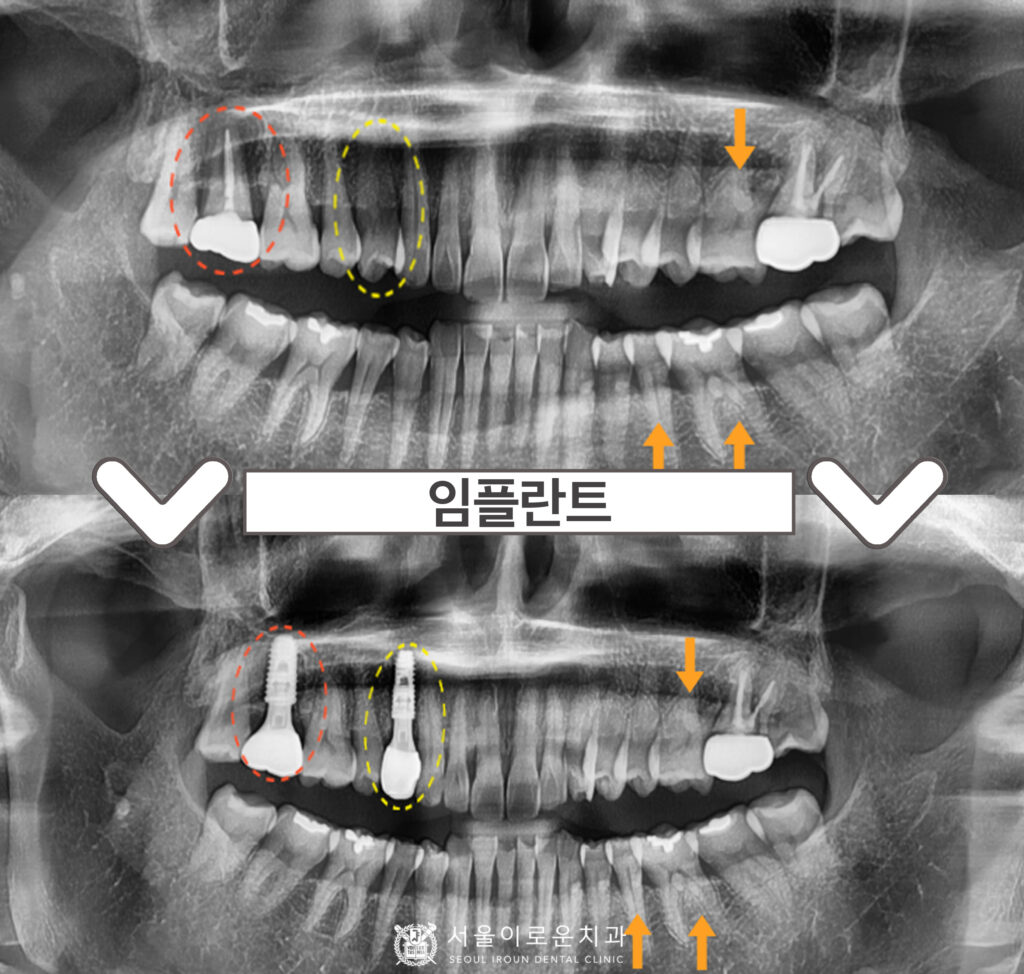

오늘 소개해 드릴 분은 60대 여성분으로,

오른쪽 위 송곳니 쪽에

딱딱한 음식을 먹었는데

치아가 갈라져서 흔들리며,

아프시다며

본.원을 찾아주셨습니다.

확인해 보았더니

노란색 동그라미 표시의

오른쪽 위 첫 번째 작은 어금니(#14)에서

불편감을 보이셨는데요.

x-ray 상으로는 크랙 라인이

또렷하게 관찰되지는 않지만

구내에서 확인하였을 때

상당히 깊게 크랙이

진행된 것으로 보였으며

타진 반응에도 통.증이 있었습니다.

안타깝게도 치아가 둘로 쪼개져

예후가 좋지 않아

발치를 해야 하는 상황이었답니다. (ㅠㅠ)

그리고 해당 치아 뿐만 아니라

다른 부위에서도

문제가 있는 부위들을

발견할 수 있었는데요…!

주황색 동그라미 표시의

오른쪽 위 두 번째 큰 어금니(#17)의

기존 보철하였던 치아가

동요도가 심하고, 뿌리까지 염증이

진행된 것을 확인할 수 있었습니다.

그리고 주황색 화살 표시의

왼쪽 위 첫 번째 큰 어금니(#26),

왼쪽 아래 두 번째 작은 어금니(#35)와

첫 번째 큰 어금니(#36)엔

치아와 잇몸 사이인

치경부 부위가 움푹 파여있는

치경부 마모증을 관찰할 수 있었는데요.

✅ 전 > 후 ✅

(2024.02.22 ㅡ> 2024.08.02)